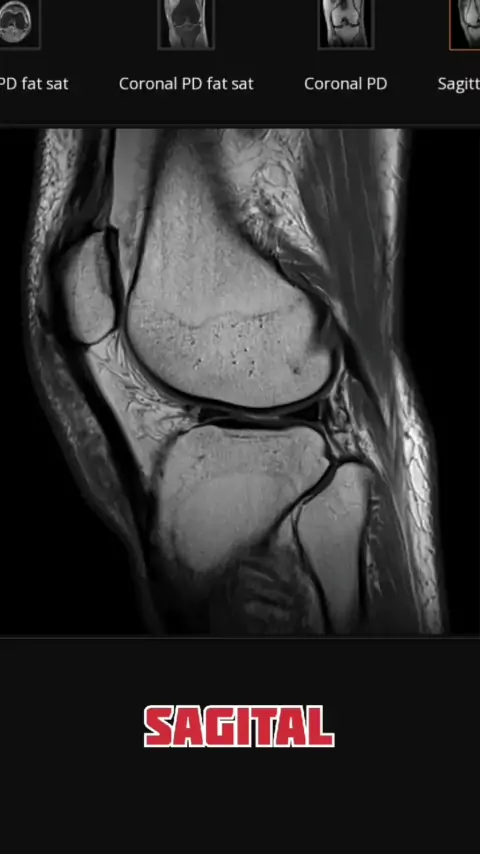

new case tibial intercondylar eminence. yuk tebak dimana kelainan nya? #fyp #infokesehatan